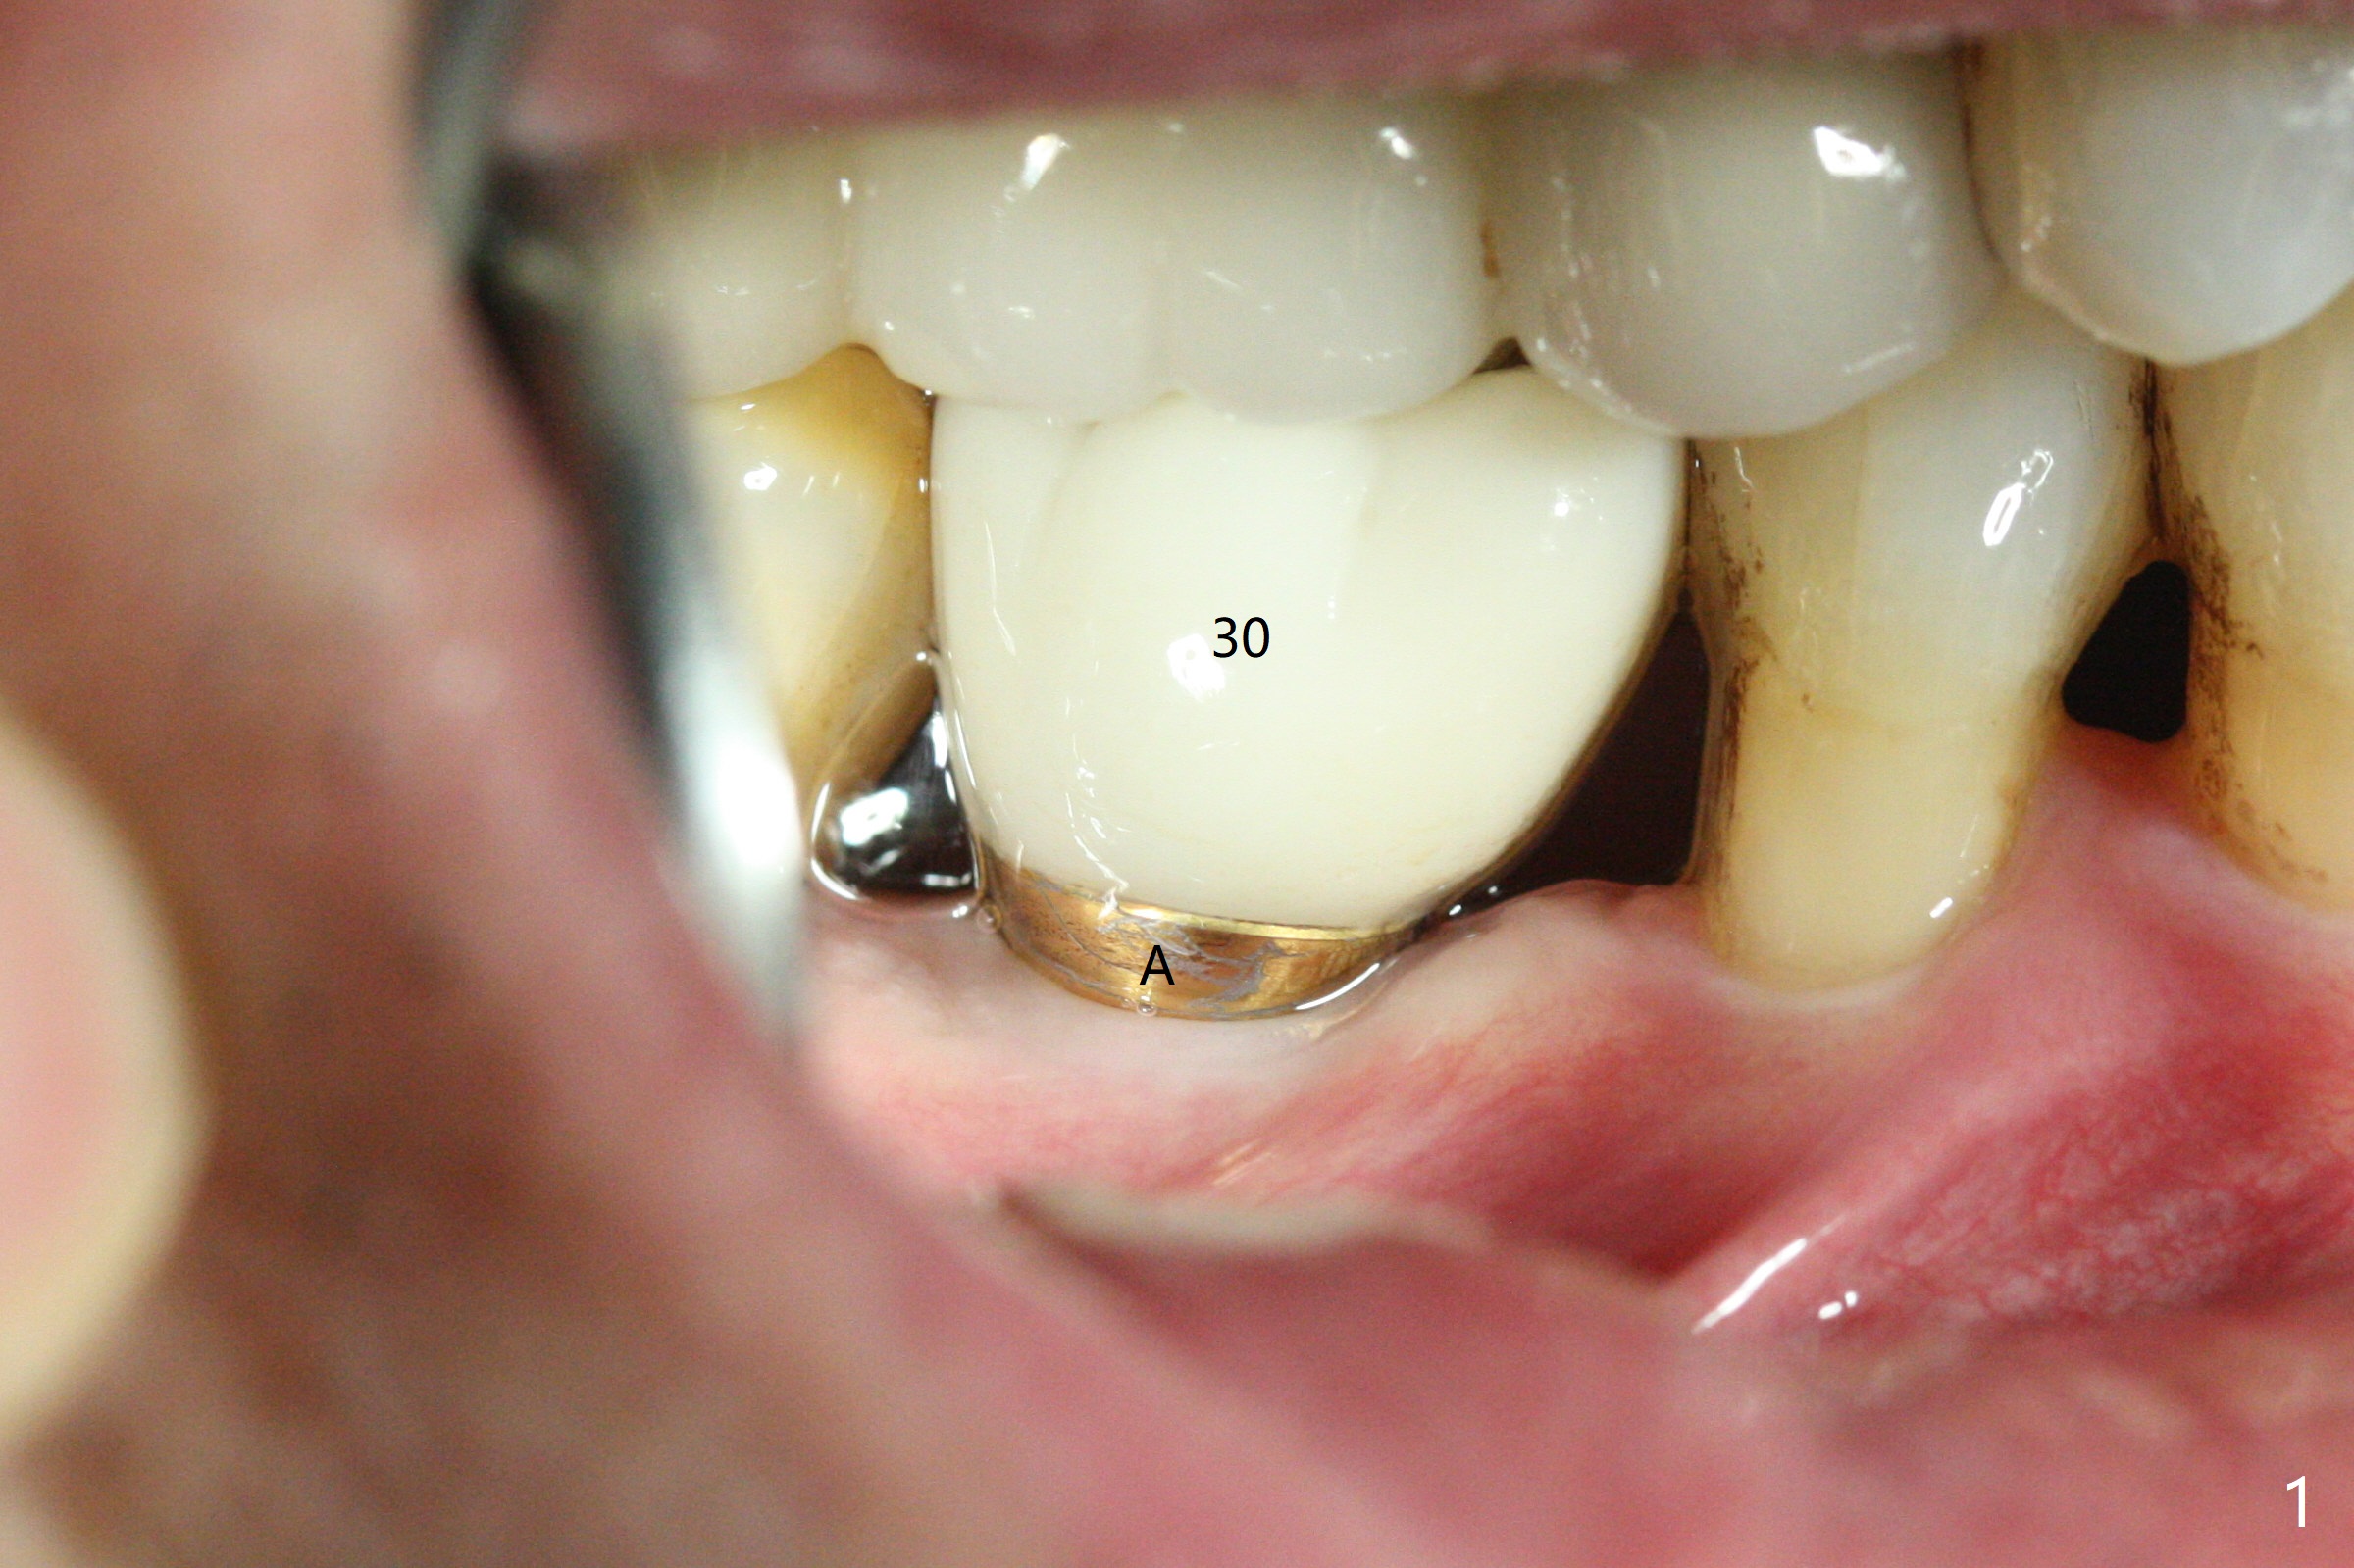

A 64-year-old man returns with history of a lump in the right submandibular region. Biopsy in a medical clinic shows inflammation. The implant crown at #30 has been cemented for ~ 4 years (Fig.1 (A: abutment)). The lingual plateau of the implant is exposed for 1-2 years asymptomatic (Fig.2 *). There is no deep lingual pocket when the crown and abutment are removed (Fig.3). Flap surgery confirms microthread exposure (circumferential, Fig.4). After removal of the microthreads with diamond bur (Fig.5), allograft (Fig.6 *), 6-month collagen membrane and a 6.5x5(3) mm healing abutment are placed. Following suturing, periodontal dressing is applied. The site remains asymptomatic 3 months postop, when an implant is placed subcrestal at #3.